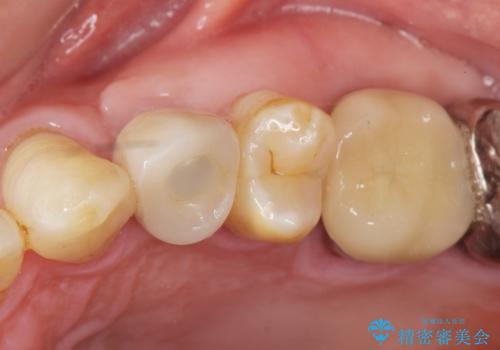

歯がわれた 抜歯してインプラント 50代男性

- 歯ぐきの腫れと痛みを主訴に来院された患者様です。

精査したところ、歯が割れており保存不可能な状態であったためやむなく抜歯しました。

患者様のご希望によりインプラント治療を行いました。